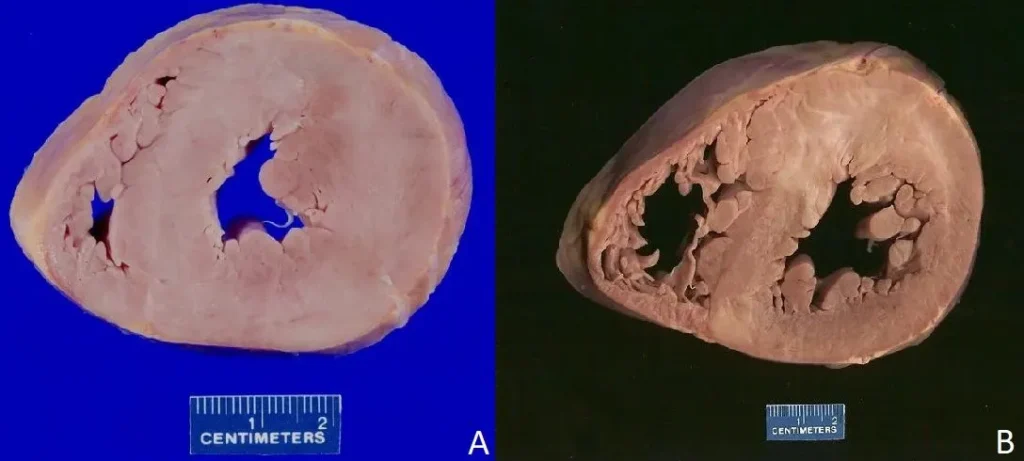

Serce z przerostem lewej komory.

Ryc. A Ryc. B – Obraz makroskopowy serca hipertroficznego. Widać pogrubienie przegrody międzykomorowej i ściany lewej komory.

Wzrost ciśnienia będzie zmianą dotychczasowych warunków pracy narządu. Serce zaadoptuje się do nich poprzez przerost, co skompensuje warunki nadciśnienia neutralizując główny problem. Dzieje się tak tylko pozornie. Początkowo, w wyniku adaptacji hipertrofii ulega mięśniówka lewej komory. Staje się wyraźnie grubsza, co widać na zdjęciu A i B. Jeżeli nie odwrócimy procesu patologicznego leżącego u podstawy tych zmian to dojdzie do usztywnienia ściany lewej komory i wtórnego poszerzenia lewego przedsionka. To zdarzenie najczęściej sprawia, że problem pacjenta staje się jawny klinicznie – dochodzi do napadowego migotania przedsionków. Skutkiem jest wysokie prawdopodobieństwo utworzenia materiału zatorowego, który opuszczając serce trafi do naczyń mózgowych dając udar niedokrwienny. Właśnie w ten sposób problem pozornie błahy może przerodzić się w skrajnie poważny. Oczywiście nie zachodzi to w zawrotnym tempie, więc czas na interwencje terapeutyczną jest znaczny. Alternatywnym scenariuszem następstw przerostu mięśnia sercowego jest jego niewydolność, gdyż wielkość serca nie przekłada się na jego jakość.